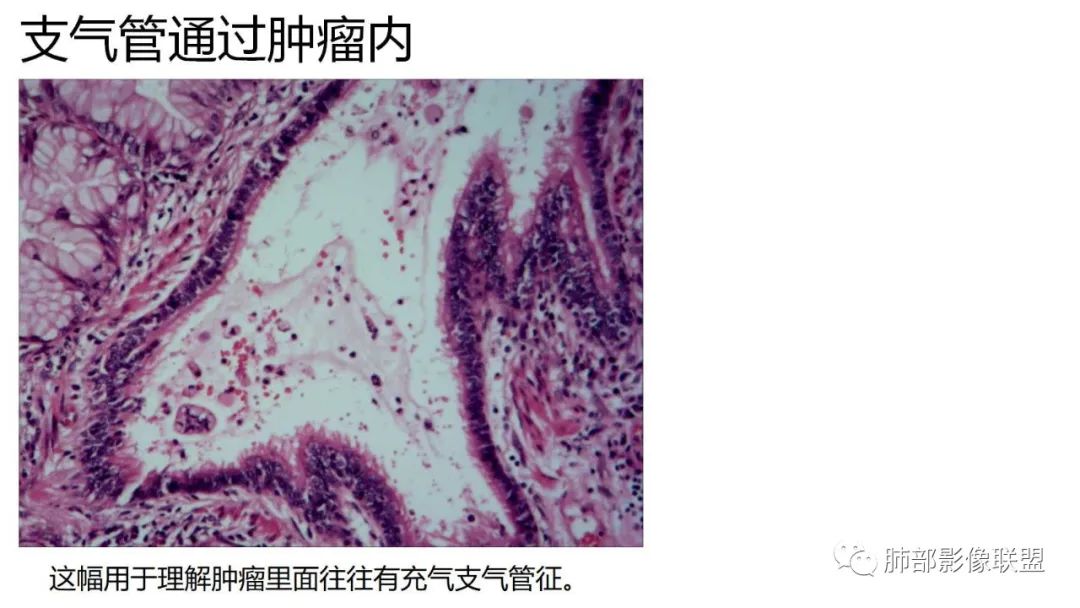

5、支气管粗细不均,呈“枯树枝征”,但与肺炎这一点鉴别不具有统计学差异。可发生支气管扩张

9.粘液腺癌的变化规律:结节缓慢发展而来,向周围播散形成斑片后可快速进展,有时支气管镜后或粘液排出后局部可形成好转的假象。病灶可沿肺泡和支气管播散。